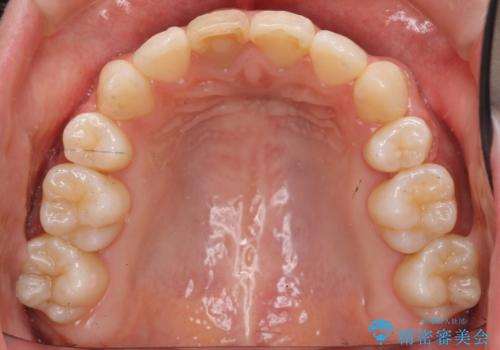

八重歯 前歯のがたがた 抜歯してワイヤー矯正

上下左右の小臼歯を抜歯し、ワイヤー矯正を行いました。

犬歯のコントロールが難しく、矯正用ミニスクリューを併用しました。

右上の前歯は変色もあり、神経の治療後にセラミックを被せる予定です。